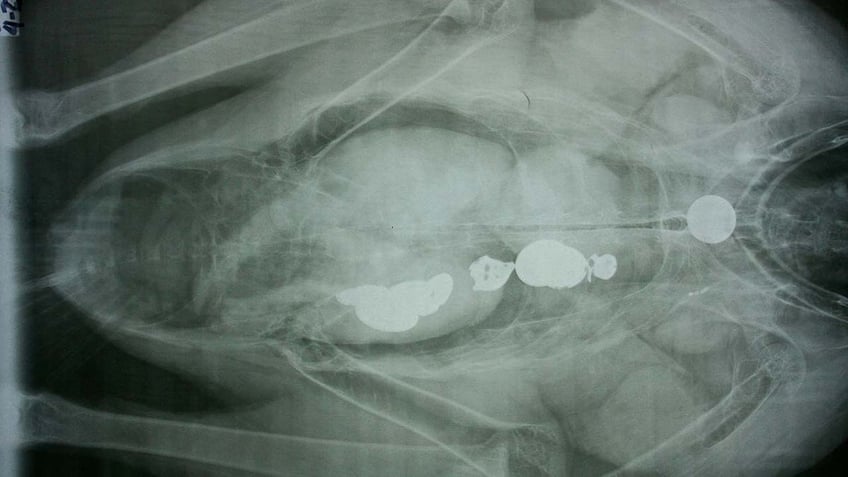

To illustrate their point, park rangers posted an X-ray image of a condor with coins lodged in its digestive tract. If the animal eats too many shiny metal objects, per the post, "it could die."

An X-ray of a condor who has swallowed several coins. Grand Canyon park staff wrote in their Wednesday Facebook post that keys thrown off the canyon as part of the popular love lock ritual could pose a health hazard to the birds. (Grand Canyon National Park)